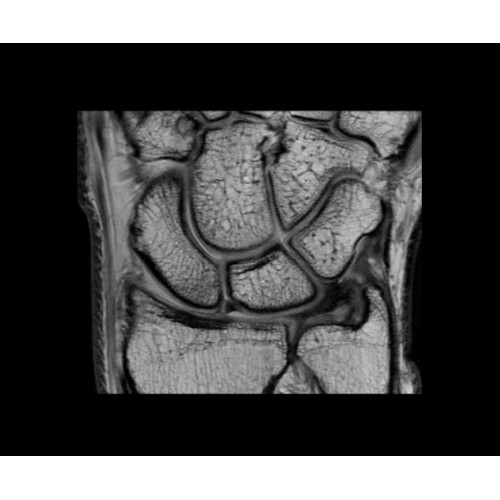

• OrthoWorks — программное решение для визуализации структур опорно-двигательного аппарата с прекрасным контрастированием тканей.